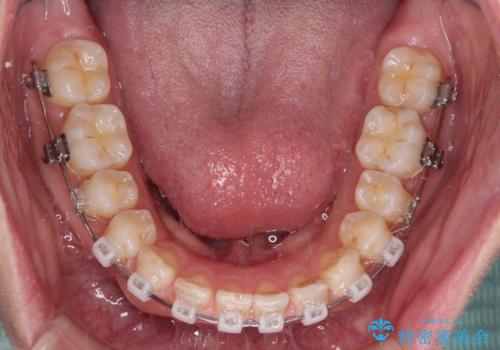

【モニター】ディープバイトを治す ワイヤー装置による矯正治療

- 顎が疲れるほどのディープバイトを気にして来院された患者様です。

手前に傾斜している奥歯を直立させながら、歯列全体の平面を均一に整えることでディープバイトを改善していくこととしました。

ディープバイトは咬合力が強いことが特徴であり、より良い仕上がりとするために、臼歯部のコントロールを行いやすいワイヤー装置を用いて矯正治療を行うこととしました。